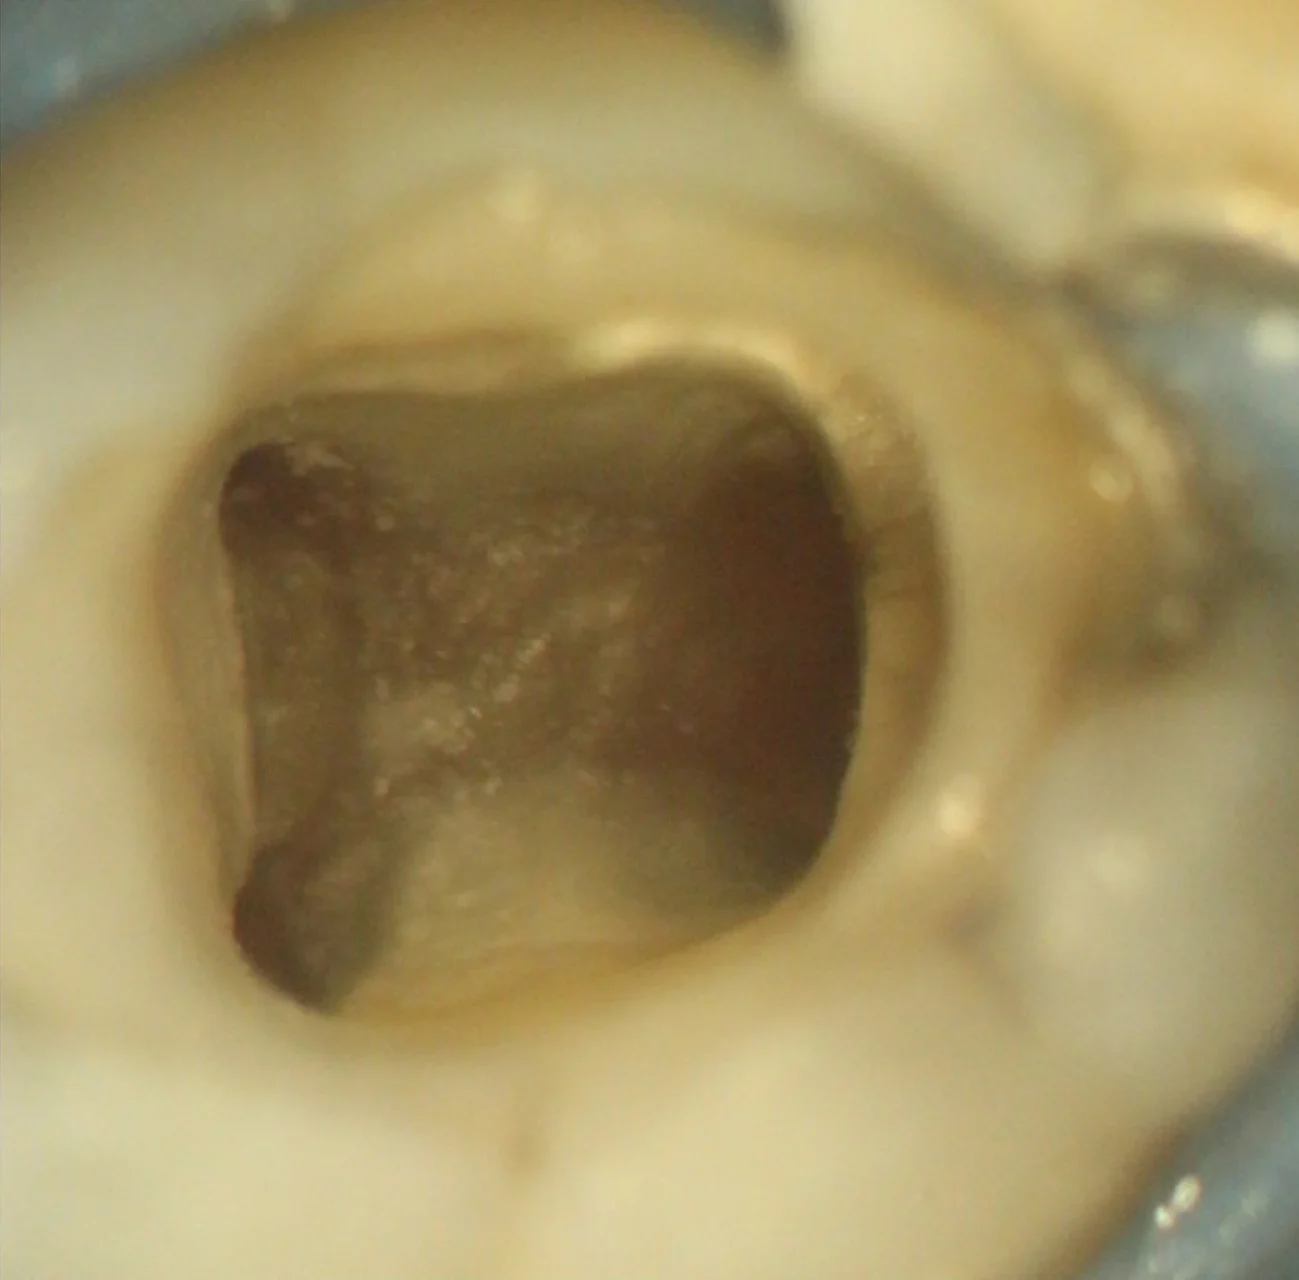

Localização de Canais Calcificados

Microscópio auxiliando na limpeza e localização de canais calcificados

Calcificação Pulpar

Após remoção do cálculo e localização dos canais

Auxílio do microscópio na localização e limpeza